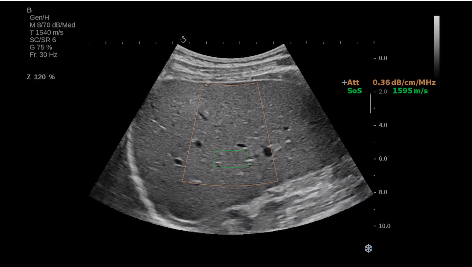

法國聲科影像(SuperSonic Imagine,SSI. Euroniex:FR0010526814)近日發(fā)表公告,宣布其研發(fā)的新一代“極速”超聲成像平臺(UltraFast Imaging),首次實現(xiàn)了肝臟的多項超聲定量評估新指標同步檢測,包括:Att PLUS,SSp PLUS和Vi PLUS等,基本涵蓋肝臟相關(guān)病理變化指征的如纖維化、脂肪變、炎癥等。據(jù)悉,此多項新技術(shù)新將搭載于新Aixplorer系列E超系統(tǒng)。

E超相關(guān)技術(shù)已被多項多中心大樣本研究證實對于肝纖維化無創(chuàng)評估有重要意義,同時也可全面應用于乳腺、甲狀腺、肝臟、前列腺、肌骨、婦科等全身各組織器官的定量評估和鑒別診斷。在慢性肝臟方面,聲科E超的肝臟相關(guān)定量診斷技術(shù)集,于2018年獲得美國FDA認證,成為FDA歷史上首次獲批的單病種超聲全面定量解決方案。

E超是在原有B超、彩超(彩色多普勒CDFI)基礎(chǔ)上研發(fā)成功的新一代超聲剪切波彈性成像系統(tǒng),是一種能夠全面應用于表淺組織、腹部臟器,血管等方面的組織彈性成像技術(shù)。根據(jù)組織硬度彈性值的不同,有效鑒別實性腫瘤的良惡性。對于惡性病變的診斷具有較高的特異性和敏感性,尤其對于甲狀腺、乳腺、前列腺等小器官,能夠完成常規(guī)超聲不能完成的組織定量分析,可以實時、全幅、全定量獲得組織彈性(硬度)信息,為鑒別腫瘤的良惡性提供客觀、量化的診斷依據(jù)。